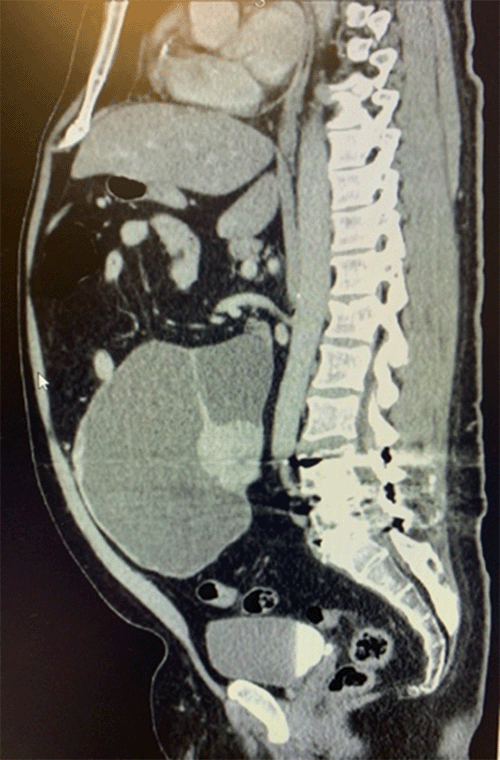

Physical examination revealed a distended abdomen with focal tenderness in the left lower quadrant and hypogastric region. A soft mass was readily palpable in this area. Abdominopelvic CT scan identified a large (30 × 14 × 17 cm) cystic mass with areas of calcification arising from either the mesentery and/or the distal small bowel (Figure 1).

Figure 1. Abdominopelvic CT Scan of Giant Cystic Mass. Published with Permission